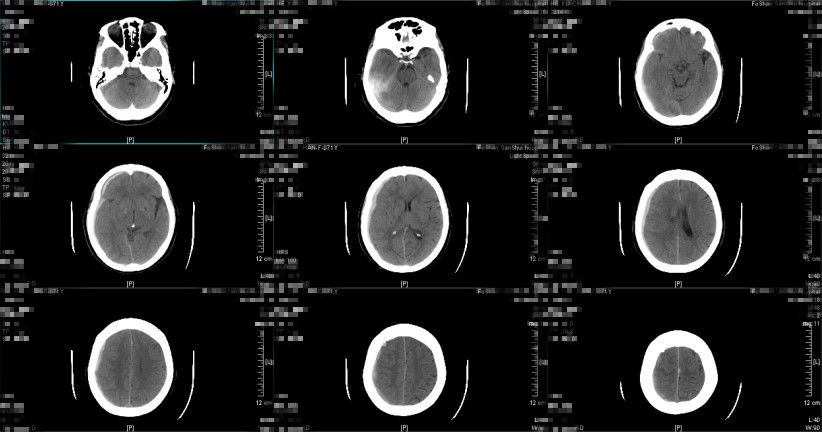

图6. 入院后第九天复查头颅CT提示:亚急性硬膜下血肿形成,血肿量较前增多。(2018-12-29 15:36:23)

患者入院后第七天至九天诉头痛较前稍有加重,以夜晚为主,无呕吐,神志仍清醒,精神状态尚可,复查头颅CT提示亚急性硬膜下血肿形成,最大厚度约0.9cm,中线向左偏移约0.5cm,环池尚清晰,右侧稍有受压,评估有硬膜下血肿继续进展的趋势,考虑与患者年龄大、长期服用氯吡格雷抗栓治疗等因素有关,详细与患者及其家属讲解病情及治疗方案,选择予以立普妥药物治疗,拟治疗1周复查头颅CT,如继续进展予外科手术治疗,根据病情动态复查头颅CT检查评估颅内情况。

患者于2019年1月3日早上8点左右出现意识障碍,神志模糊,GCS评分10分,考虑硬膜下血肿继续增多、颅压高引起,予20%甘露醇250ml 快速静滴并同时送至CT室复查头颅CT提示(图7、图8):亚急性硬膜下血肿继续较前增多,最大厚度约2cm,中线向左偏移大于1cm,环池受压,有明确的手术指征。经脱水药物处理后,患者神志转清,GCS评分上升到14分,再次与患者及其家属讲解病情及治疗方案,选择予微创手术治疗方案。遂于当天早上9点左右行右额部微创针穿刺亚急性硬膜下血肿引流术,术中予生理盐水反复置换冲洗,术后行定时开放、夹闭引流,行阶梯性减压,利用脑复张促进血肿引流。

图7.(2019-01-03 08:34:45)

图8